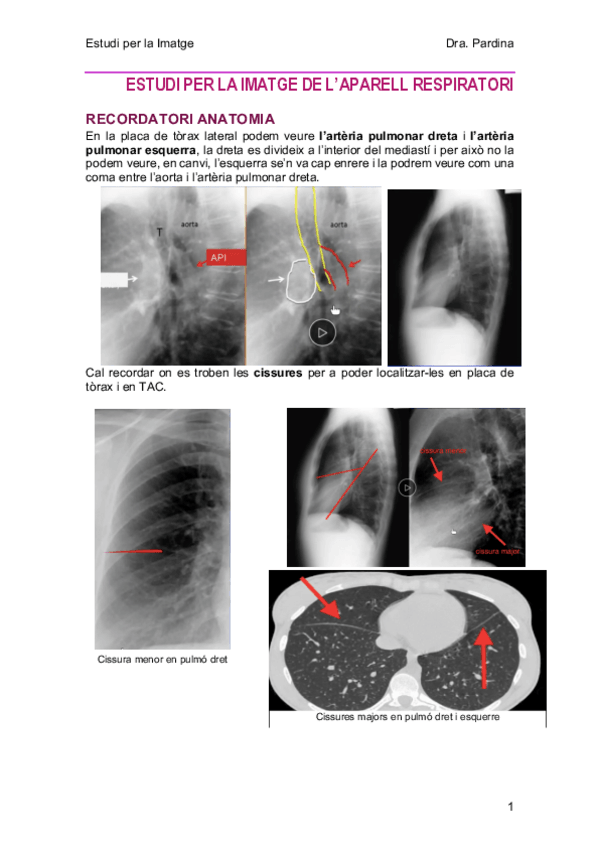

3-AparellRespiratori.pdf